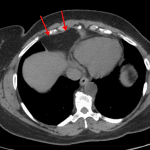

Age: 51

Sex: Female

Indication: Cough

Findings

- Clearly marginated hazy density along the anteromedial right lung base

Diagnosis

- Prominent pericardial fat

No evidence of acute cardiopulmonary disease.

Clearly marginated hazy density along the anteromedial right lung base likely represents prominent pericardial fat.